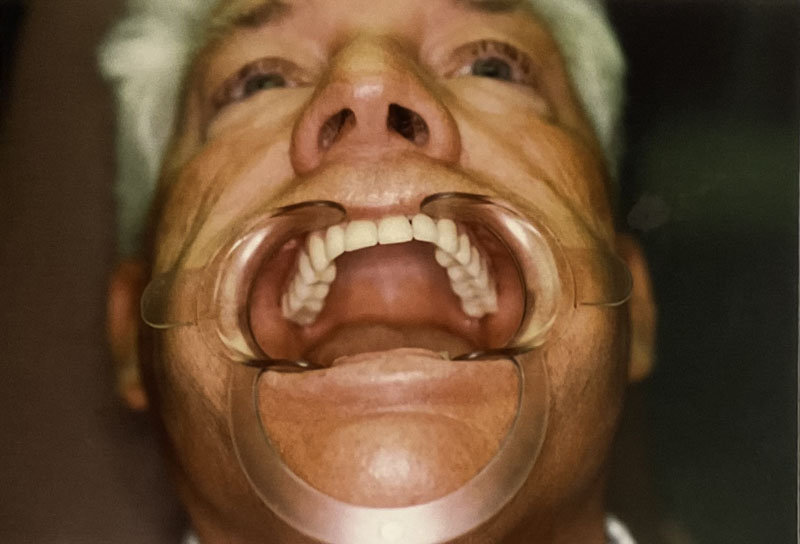

Invisalign® Clear Aligners

Case Highlight

Before

After